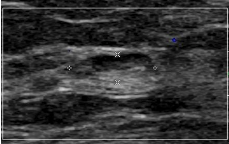

Intramammary lymph node

Lymph node within breast tissue

• Can be benign or malignant

• Common

• Usually upper outer quad

Solitary/ multiple nodes

Benign features: oval, hypoechoic to breast tissue, echogenic vascular hilum

Malignant features: round, very hypoechoic, homogeneous, >1cm